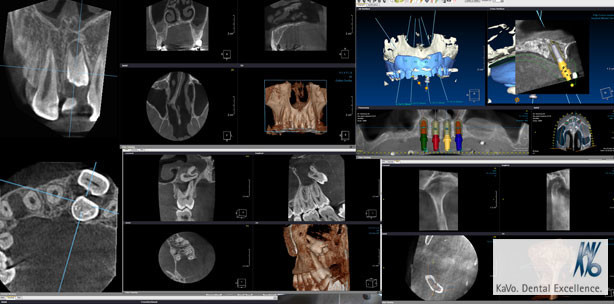

Webinar: DVT-Aufnahmen problemlos auswerten

Foto: © KaVo

Welches sind die wichtigsten Kriterien, auf die man bei der Diagnostik und Befundung von DVT-Aufnahmen achten muss?

In unserem Webinar am 26. September 2012, 17 Uhr wird anhand von praktischen Fallbeispielen der diagnostisch und therapeutisch optimale Umgang mit DVT-Aufnahmen beschrieben. Die wichtigsten anatomischen Landmarken und deren pathologische Veränderungen werden erläutert, so dass Sie die neu erworbenen Kenntnisse unmittelbar in Ihre tägliche Arbeit einfließen lassen können!

Referent ist der erfahrene Röntgenspezialist PD Dr. Dirk Schulze aus Freiburg im Breisgau.